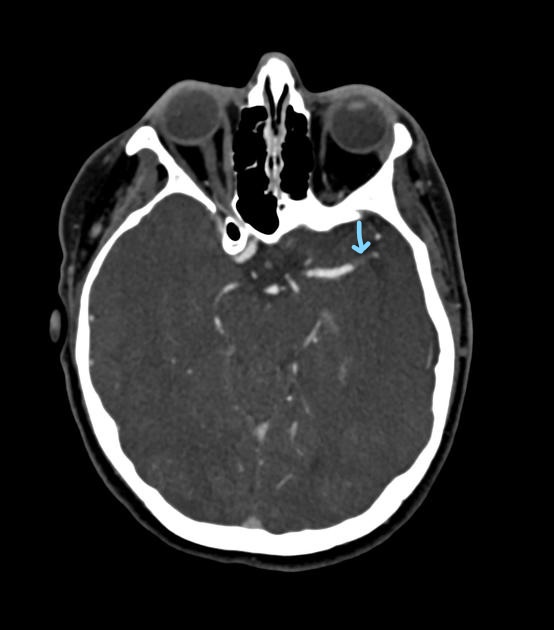

What does a hyperdense MCA sign indicate?

An occlusive thrombus in the middle cerebral artery.

Should CTA proceed if a hyperdense artery is seen but no bleed is present?

Yes.